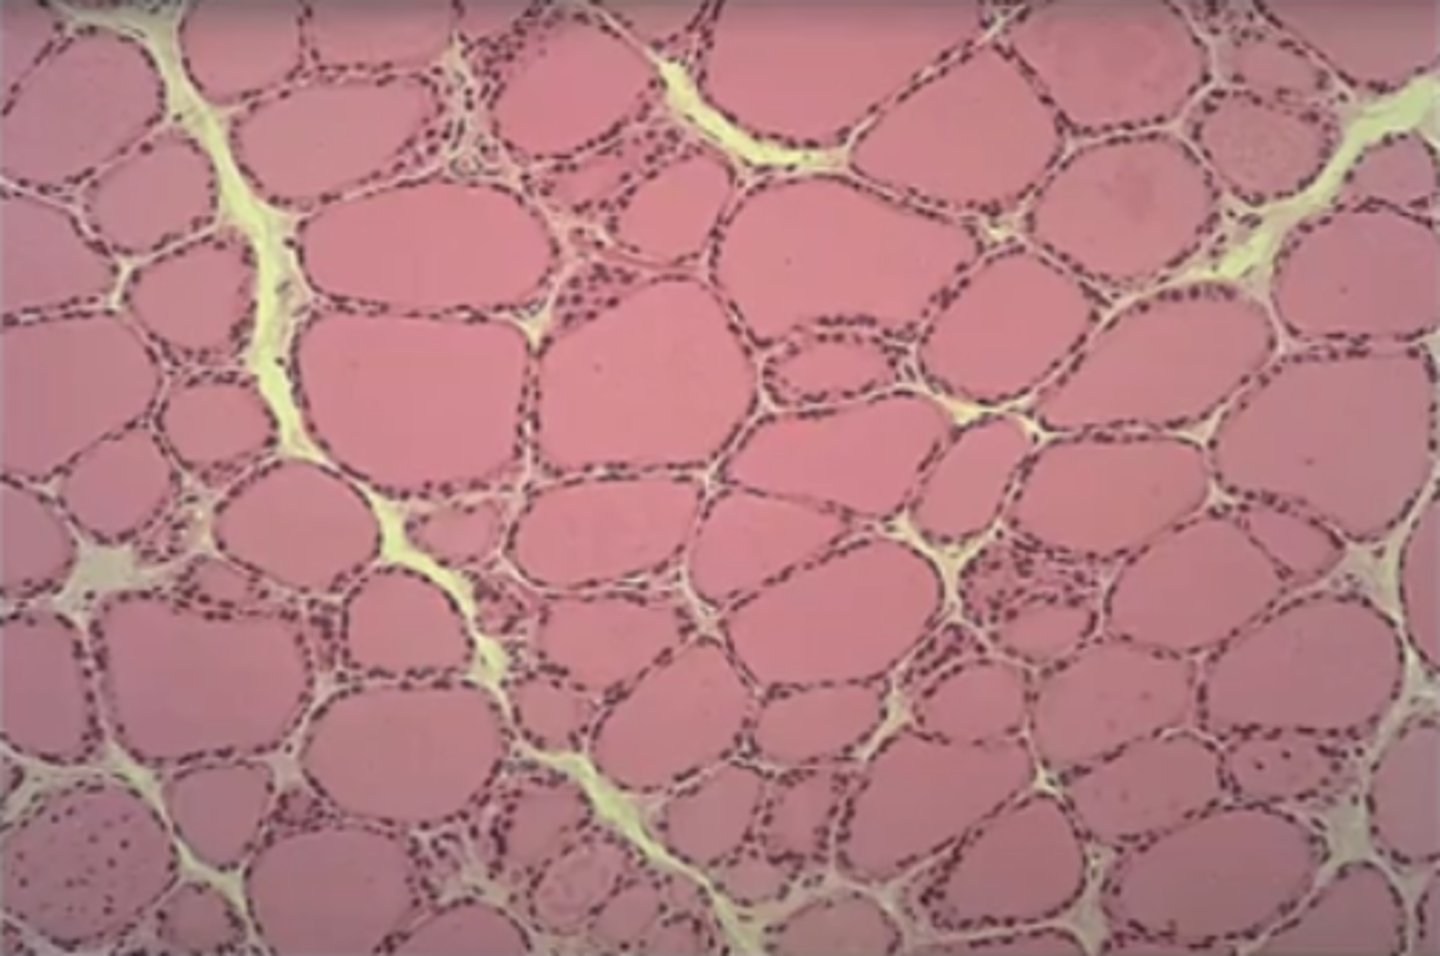

Thyroid gland

What is this?

calcitonin

What hormone does thyroid secrete?